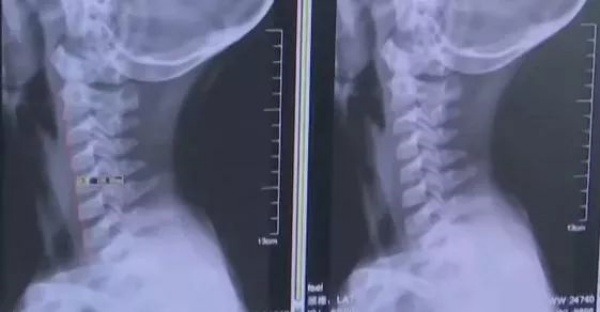

Vài ngày trước, cậu bé cảm thấy đau đầu, đau cổ cổ và chóng mặt.Sau khi mẹ cậu phát hiện ra, đã bảo cậu không được chơi game trên điện thoại di động nữa, điều này khiến cậu bé rất sợ hãi. Sau đó, mặc dù các triệu chứng khó chịu vẫn còn, cậu bé vẫn lén lút cầm điện thoại chơi game, nói dối mẹ rằng mình không còn dùng điện thoại nữa. Tuy nhiên, hai tuần sau, các triệu chứng ngày càng nghiêm trọng và đã đến mức không thể chịu đựng nổi, bé trai 14 tuổi ói với mẹ về sự khó chịu của mình. Người mẹ vội vàng đưa con đến bệnh viện để điều trị. Chụp X-quang cột sống cổ cho thấy: đốt sống cổ có độ cong sinh lý bất thường, thoái hóa đốt sống cổ. Sau khi biết về tình hình của nam sinh, bác sĩ đã nói với cậu bé rằng hãy tránh cúi đầu trong một thời gian dài, nếu không thì cột sống càng ngày càng thoái hóa đến mức không thể chữa trị được.